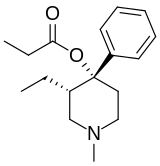

Phenylpiperidines

- Pethidine (meperidine)

- Ketobemidone

- MPPP

- Allylprodine

- Prodine

- PEPAP

- Promedol